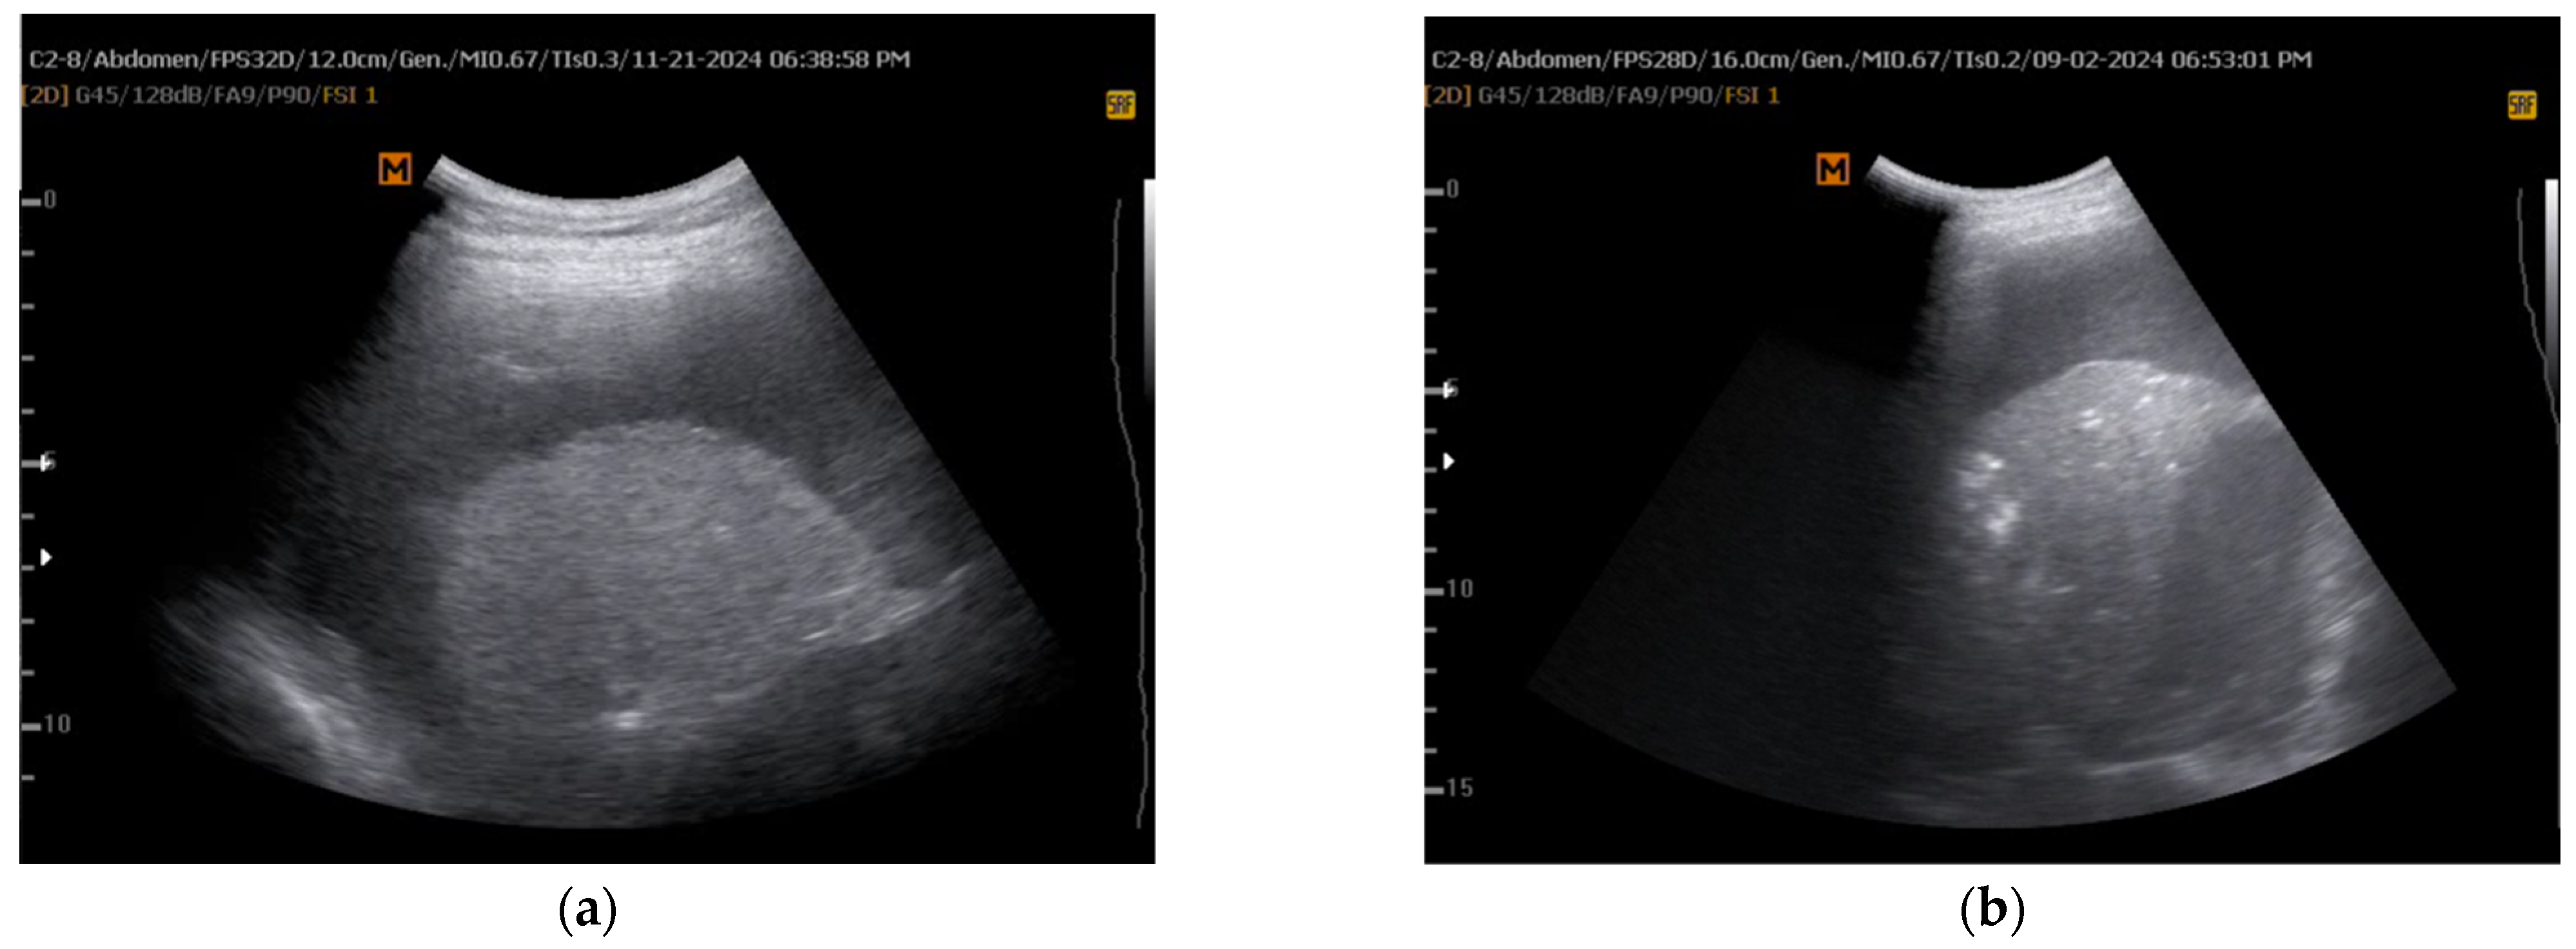

5.1. M-Mode Sinusoid Sign Assessment

| Salamonsen et al. [15] | 2014 | Assess M-mode US for predicting NEL | Prospective observational study | 81 patients with MPE | M-mode, speckle tracking imaging (STI) | M-mode displacement <0.8 mm predictive of NEL | Allowed pre-drainage identification of entrapped lung | Some misclassification due to incomplete drainage |

| Leemans et al. [17] | 2018 | Investigate predictors of successful talc pleurodesis in malignant pleurisy | Retrospective study | 155 patients undergoing talc pleurodesis | M-mode | M-mode displacement <2 mm correlated with pleurodesis success (91% sensitivity, 88% specificity) | Highlighted role of M-mode in predicting pleurodesis success | Retrospective design, limited validation cohort |

| Khatim et al. [22] | 2022 | Diagnosis of NEL using TUS | Case report | 1 patient with small cell lung cancer and recurrent MPE | M-mode | Blunted cardiophasic variability indicated NEL, confirmed by post-drainage imaging | Highlighted importance of pre-procedural TUS assessment for NEL | Single case, limited generalizability |

| Petersen et al. [23] | 2024 | Compare M-mode, B-mode, and SWE for NEL prediction | Prospective observational | 49 patients with suspected MPE | M-mode, B-mode, 2D shear wave elastography (SWE) | M-mode had highest AUC (0.81) for NEL prediction | Reinforced M-mode as core tool for pleural disease assessment | Small sample, single-center variability |